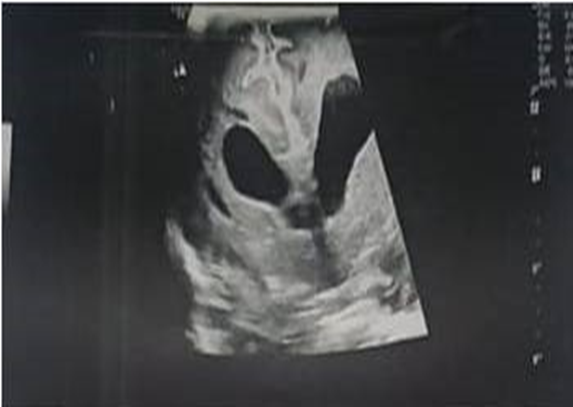

Figure 3: Trans-fontanellar ultrasound

This is a newborn male, from an unrelated marriage, of a 21-year-old mother, with no particular pathological history, the pregnancy was singleton well monitored, carried out at 36 weeks of amenorrhea plus 4 days according to the first trimester ultrasound, the delivery was vaginal and the Apgar score increased from 6/10 to 8/10 from the first to the fifth minute. The patient was hospitalized, on the first day of life, for an early neonatal infection with pulmonary localization and a weak sucking reflex associated with a polymalformative syndrome made up of facial dysmorphism, spina bifida, anal prolapse and limb anomalies. The patient weighed, at birth, 1680g (-2DS) with a height of 34 cm (-2DS) and a head circumference of 29 cm (<2DS>